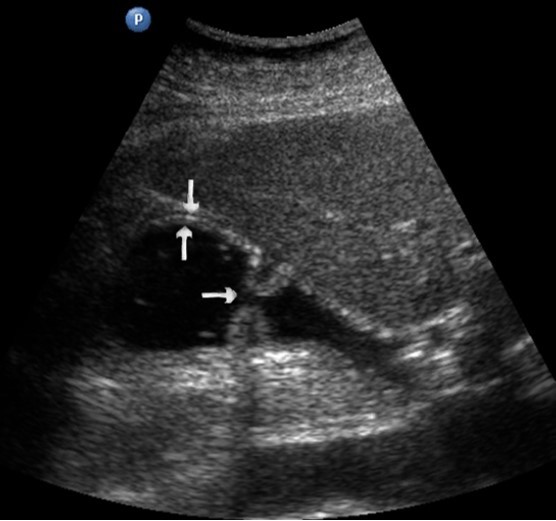

The polypoid type of gastric cancer was observed in 3 (4,9±2,8%) cases, the ulcerative type – in 18 (29,5±5,8%), the infiltrative ulcerative type – in 27 (44,3±6,4%) and the diffuse infiltrative type – in 13 (21,3%±5,2%) cases respectively (Table 2). On the echogram, the tumor was

Visualized as a polypoid formation on a wide base above the gastric mucosa of a non-uniform structure, an irregular surface (Figure 5, Figure 6, Figure 7).

Figure 5.The polypoid type of gastric carcinomas for T3 stage. On the posterior wall of the antrum, a polypoid formation with a fuzzy contour is visualized, the image of the mucous and serous membranes (arrows) is discontinuous.